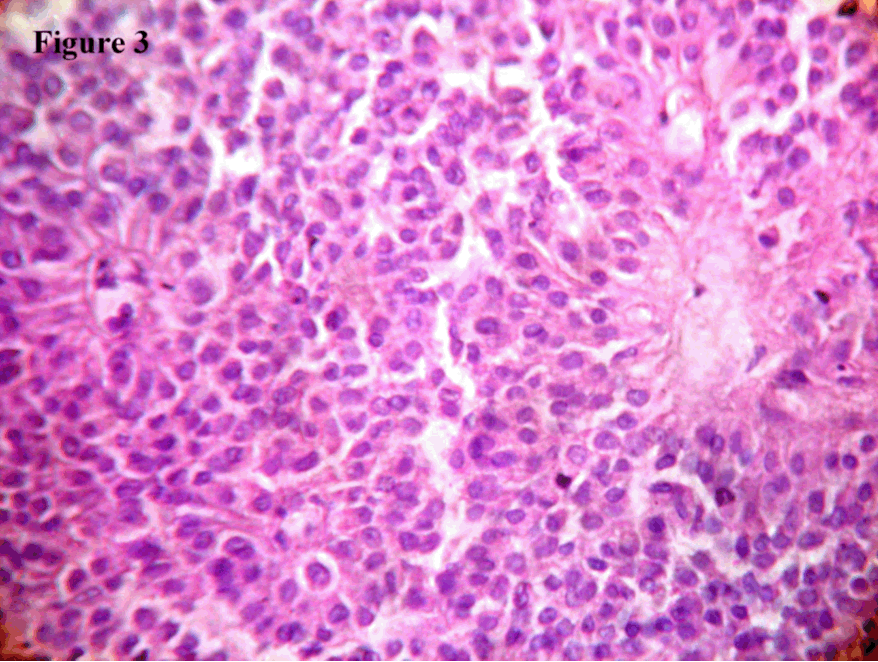

A 19-year-old female presented to the out-patient department of general surgery with complaints of dragging sensation in the upper part of the abdomen with epigastric tenderness. Upper GI endoscopy was within normal limits. CT scan showed an 8.34x7.22 cm well encapsulated, complex, heterogeneous mass with cystic and solid components in the head of the pancreas without evidence of invasion (Figure 1). CT-guided FNAC was performed. Subsequently, the patient was admitted in the department of Gastroenterology and operated with Whipple' operation and the specimen sent to our department for confirmation of the diagnosis and extent of invasion.

Figure 1: CT scan showing encapsulated, complex, heterogeneous mass with cystic and solid components in the head of the pancreas.